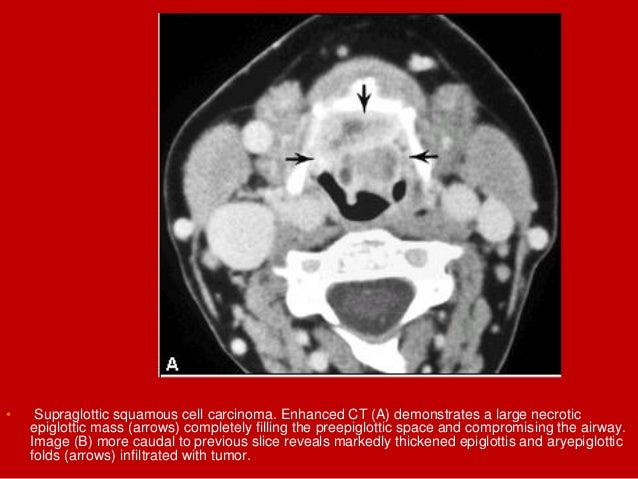

16. 16. • Supraglottic squamous cell carcinoma. Enhanced CT (A) demonstrates a large necrotic epiglottic mass (arrows) completely filling the preepiglottic space and compromising the airway. Image (B) more caudal to previous slice reveals markedly thickened epiglottis and aryepiglottic folds (arrows) infiltrated with tumor.

17. 17. • Supraglottic squamous cell carcinoma. Enhanced CT (A) demonstrates a large necrotic epiglottic mass (arrows) completely filling the preepiglottic space and compromising the airway. Image (B) more caudal to previous slice reveals markedly thickened epiglottis and aryepiglottic folds (arrows) infiltrated with tumor. A metastatic lymph node is also identified (asterisk).